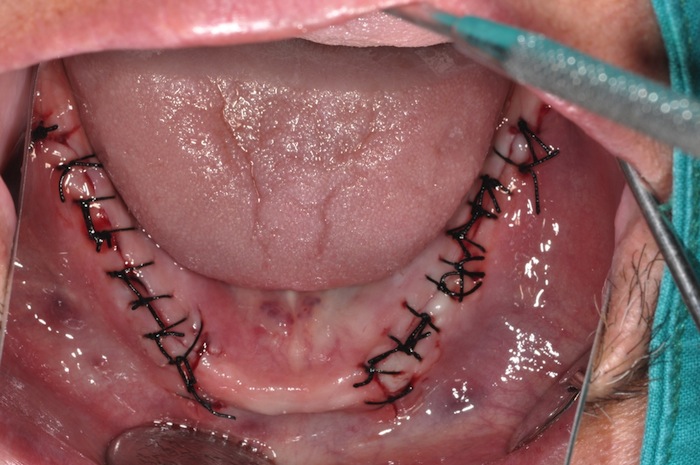

Este equipo de trabajo del grupo de Investigación en eLearning y Modelos Inteligentes de la institución de enseñanza superior desarrolló un ambiente virtual de entrenamiento médico con uso de dispositivos hápticos, construido para que los estudiantes puedan manipular instrumental y realicen las tareas de sutura empleando ambas manos, aplicando y percibiendo las fuerzas necesarias, lo más cercanas a la realidad.

Los elementos que comprende SutureHap son: Simulación de piel dinámica, con un corte previamente realizado, generación de fuerza de retroalimentación (haptic rendering), hilo que interactúa en el ambiente virtual con la capacidad de anudarse y tensar la piel e instrumental médico utilizado para sutura (aguja curva, pinza porta aguja, pinza de disección para sujetar la piel y tijera para cortar el hilo); además de facilitar la posibilidad de homologar y repetir dichas prácticas o experiencias las veces que sea necesario.

Los resultados con SutureHap son prometedores, de acuerdo con los médicos que han supervisado el trabajo y podría poner fin de una vez por todas a la controversia que genera el uso de animales en prácticas médicas. "Lo que queremos es poner una tecnología accesible para montar uno o varios laboratorios para que a cualquier hora y las veces que sea necesario, los estudiantes puedan practicar", concluyó Noguez.